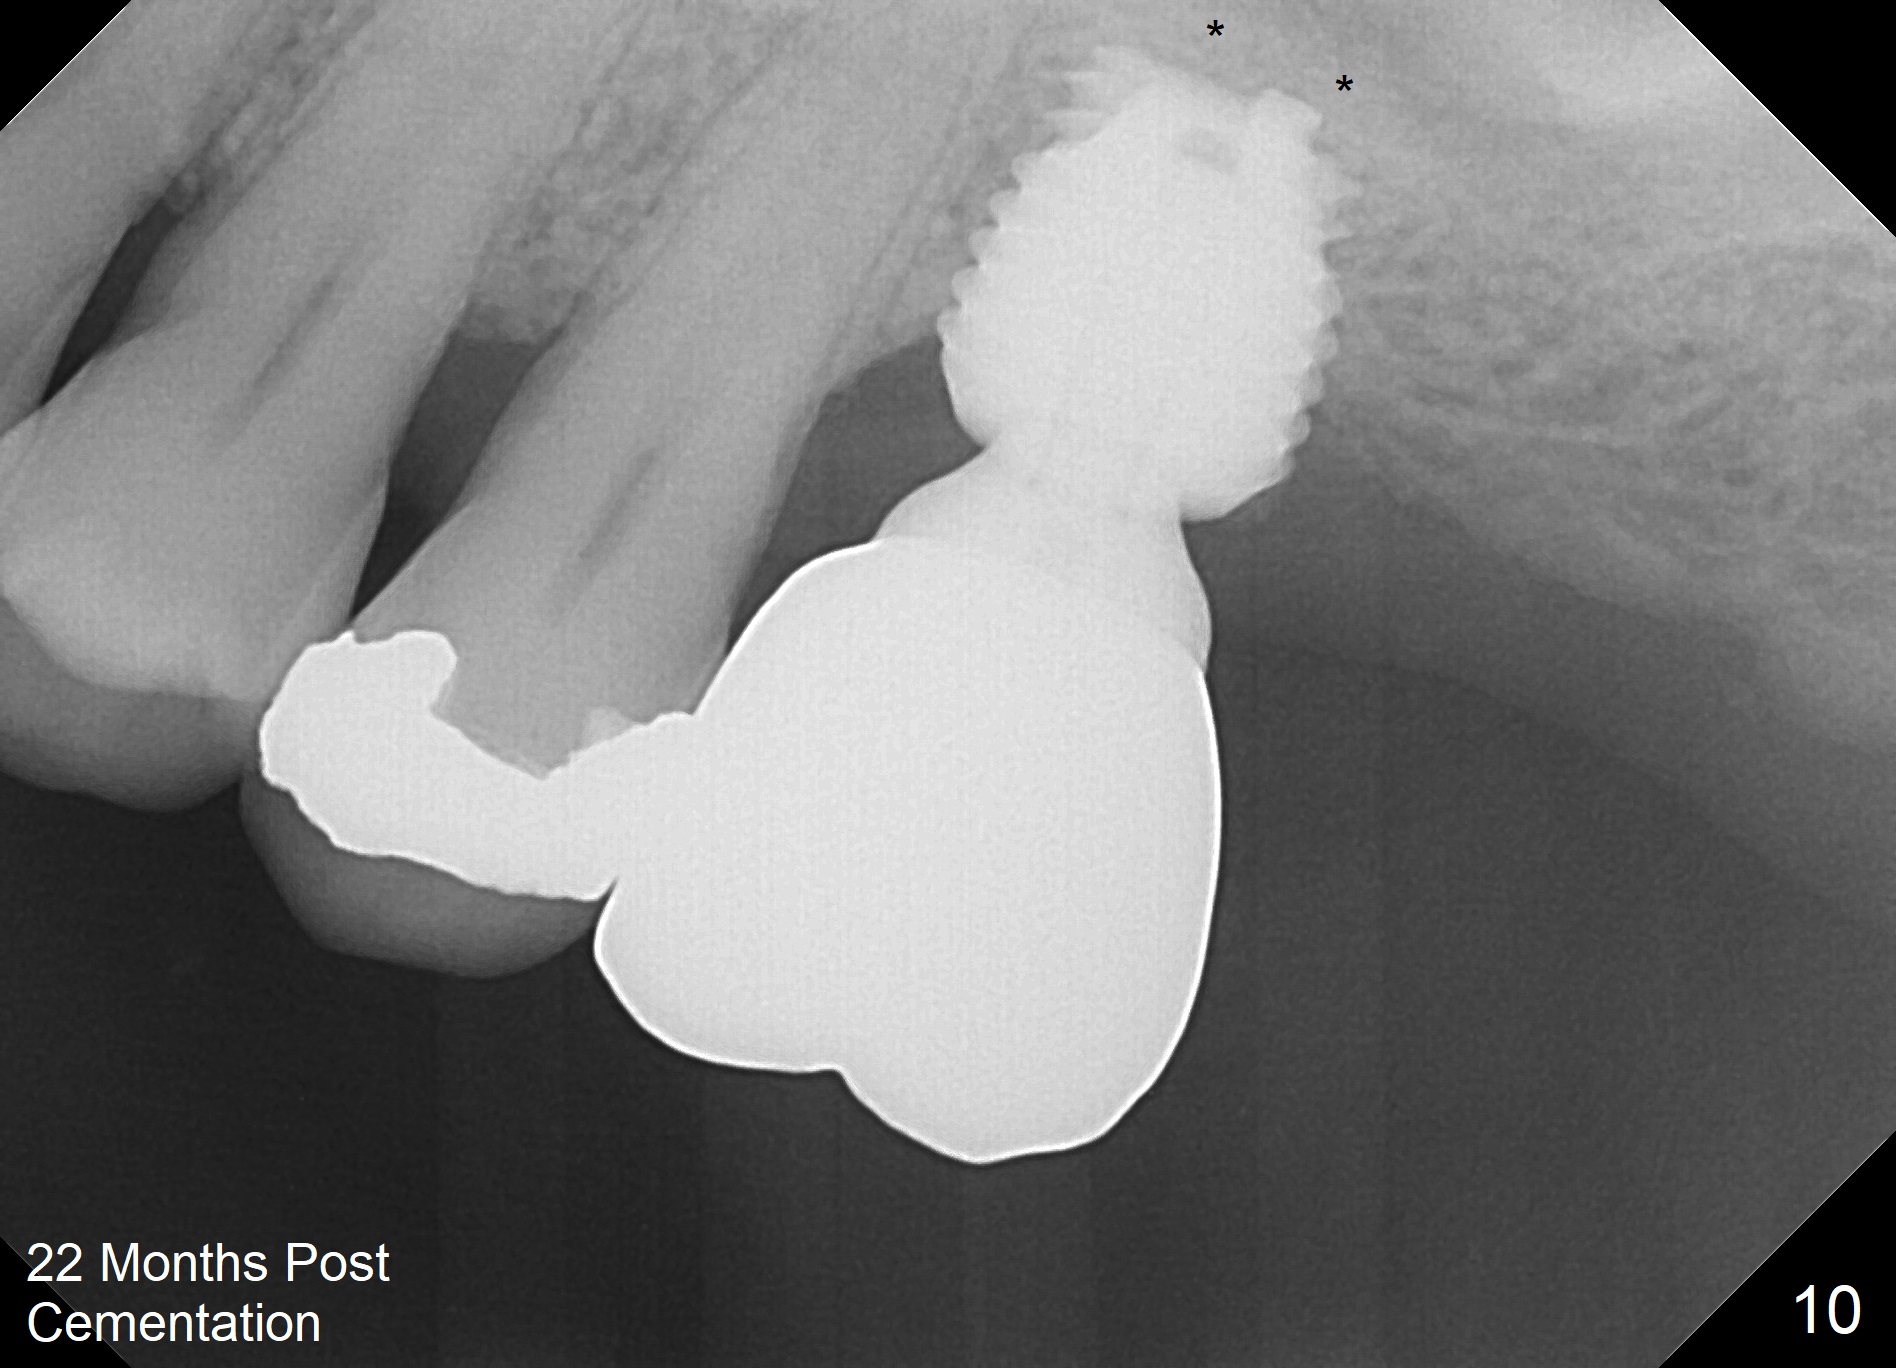

When the patient returns for impression 6.5 months postop, the provisional has dislodged because of the short abutment (Fig.7 A (6.5x4(2) mm). A longer one is placed (6.5x5(3) mm). When he returns for crown cementation 8.5 months postop, the provisional is retentive. The distal implant plateau is still exposed. Post-cementation panoramus shows that the distal 3 threads are not covered by the bone and that the crown/implant ratio is 5:3 (Fig.8). Implants are recommended at #3 and 30 (Fig.9). There is a distinct layer of bone apical to the implant at #14 22 months post cementation (Fig.10 *). In spite of exposure of 2-3 threads distally, there is no sign of peri-implantitis. It appears that the implant is subgingival (Fig.11 (BW) white dashed line: gingival margin). The implant remains infection free 3 years 10 months post cementation (Fig.12) due to the thick gingiva and good oral hygiene.